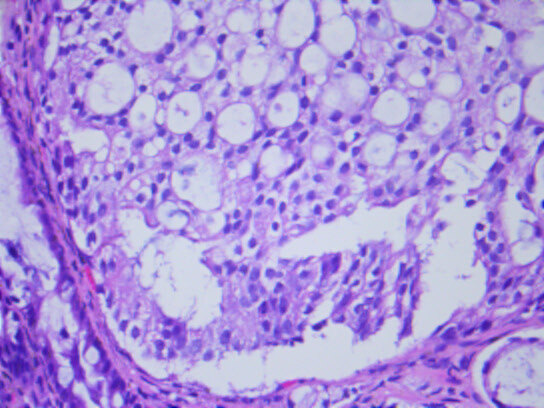

几天前,入我院行肠镜检查,并活检,显微镜下可见癌浸润于直肠粘膜之间。

最终,我们以上述HE形态为线索,老年男性,直肠占位,为XY坐标,我们初步音箱诊断就是前列腺腺泡腺癌浸润至前列腺腺外,累及直肠并形成肿块,浸润直肠全层至粘膜内。